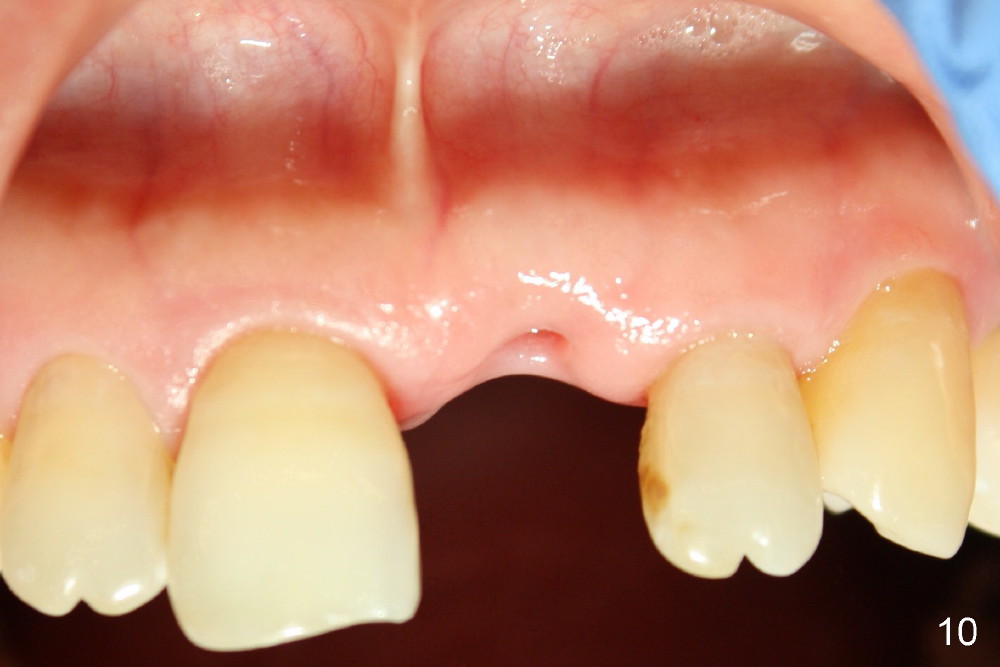

A 60-year-old lady had an abscess mesial to #9 six years ago (Fig.1,2 <), treated as a perio lesion by laser (Fig.3) and osseous surgery without bone graft (Fig.6, followed by CT exam revealing semi-circumferential bone loss (Fig.4,5). When the perio treatment failed, attention was paid to endo aspect (Fig.7-9). In fact the pulp was found to be vital when access to root canal therapy was made. As expected, the treatment failed again. The palatal fistula persisted. The infection was suspected to be a source of remote immediate implant site (#30). The tooth #9 was extracted. It appears that there is a semilunar crack line in the linguomesial root (Fig.12). When the socket healed 2 weeks post extraction (Fig.10), the #30 buccal defect was debrided with bone graft. There was no bone resorption 4 weeks post extraction (Fig.11); a 4.5x17 mm implant was placed (Fig.13-15). An immediate provisional was fabricated (Fig.16-18). Fig.19,20 were taken 3 months post implantation and 7 months post cementation, respectively. Dense bone forms around the implant coronally 4 years 5 months post cementation (Fig.21), while the gingiva is healthy palatally (Fig.22) and buccally (Fig.23).